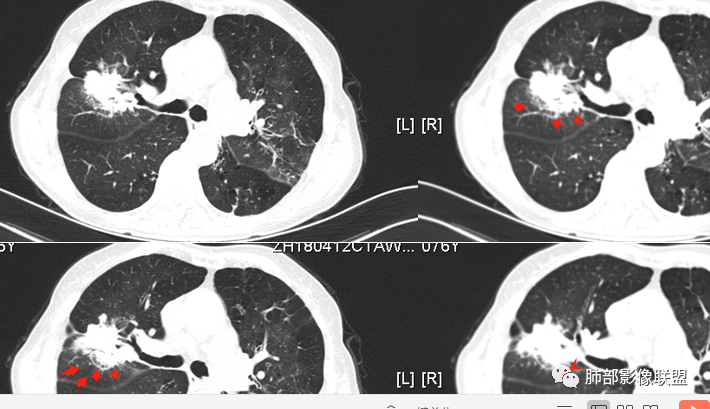

红星:    女性68岁,右肺上叶前段结节,将近7年的时间明显长大,表现出分叶毛刺及支气管截断伴胸膜凹陷,增强明显的不均匀强化,纵隔内多发的淋巴结肿大。左肺多发的斑点及条索状间质改变。考虑右肺上叶前段恶性病变,腺癌的可能性大。鉴别诊断结核或炎性肉芽肿。

宇宙:  右肺上叶不规则肿块,较8年前结节明显增大,可见分叶,毛刺,胸膜牵拉,边缘清晰磨玻璃影,上叶后段支气管堵塞,不均匀延迟强化,有坏死,纵隔淋巴结增大,考虑恶性,腺癌,鉴别炎性肉芽肿

孔儿 :   老年女性,右肺上叶前段结节8年复查明显增大,收缩力强,分叶,毛刺,邻近胸膜牵拉,部分支气管截断,周围见边界清晰磨玻璃成分,增强扫描呈不均匀强化,考虑恶性肿瘤,浸润性腺癌可能性大。

8年病史,病灶内部结构紊乱,mGGN,边缘清楚,分叶、毛刺、胸膜凹陷——腺癌

南边:   深分叶,胸膜凹陷在病灶凹陷处, 支气管近端截断

南边:   边界清楚GGO

南边:   毛刷南边:考虑恶性,进展,支持腺癌

1、老年女性,肺气肿背景,咯血多年,肿瘤标志物升高。    2、右肺上叶不规则结节影,八年后进行性增大为肿块,边缘深分叶、毛刺、棘状突起、胸膜牵拉,相应支气管壁增厚阻塞;周围局部见边界清楚的磨玻璃影;近胸壁侧见凹陷,整体呈外朝内生长。增强扫描呈不均匀明显强化,其内见坏死区,边界欠清。    3、右侧胸腔积液。纵隔见增大淋巴结。